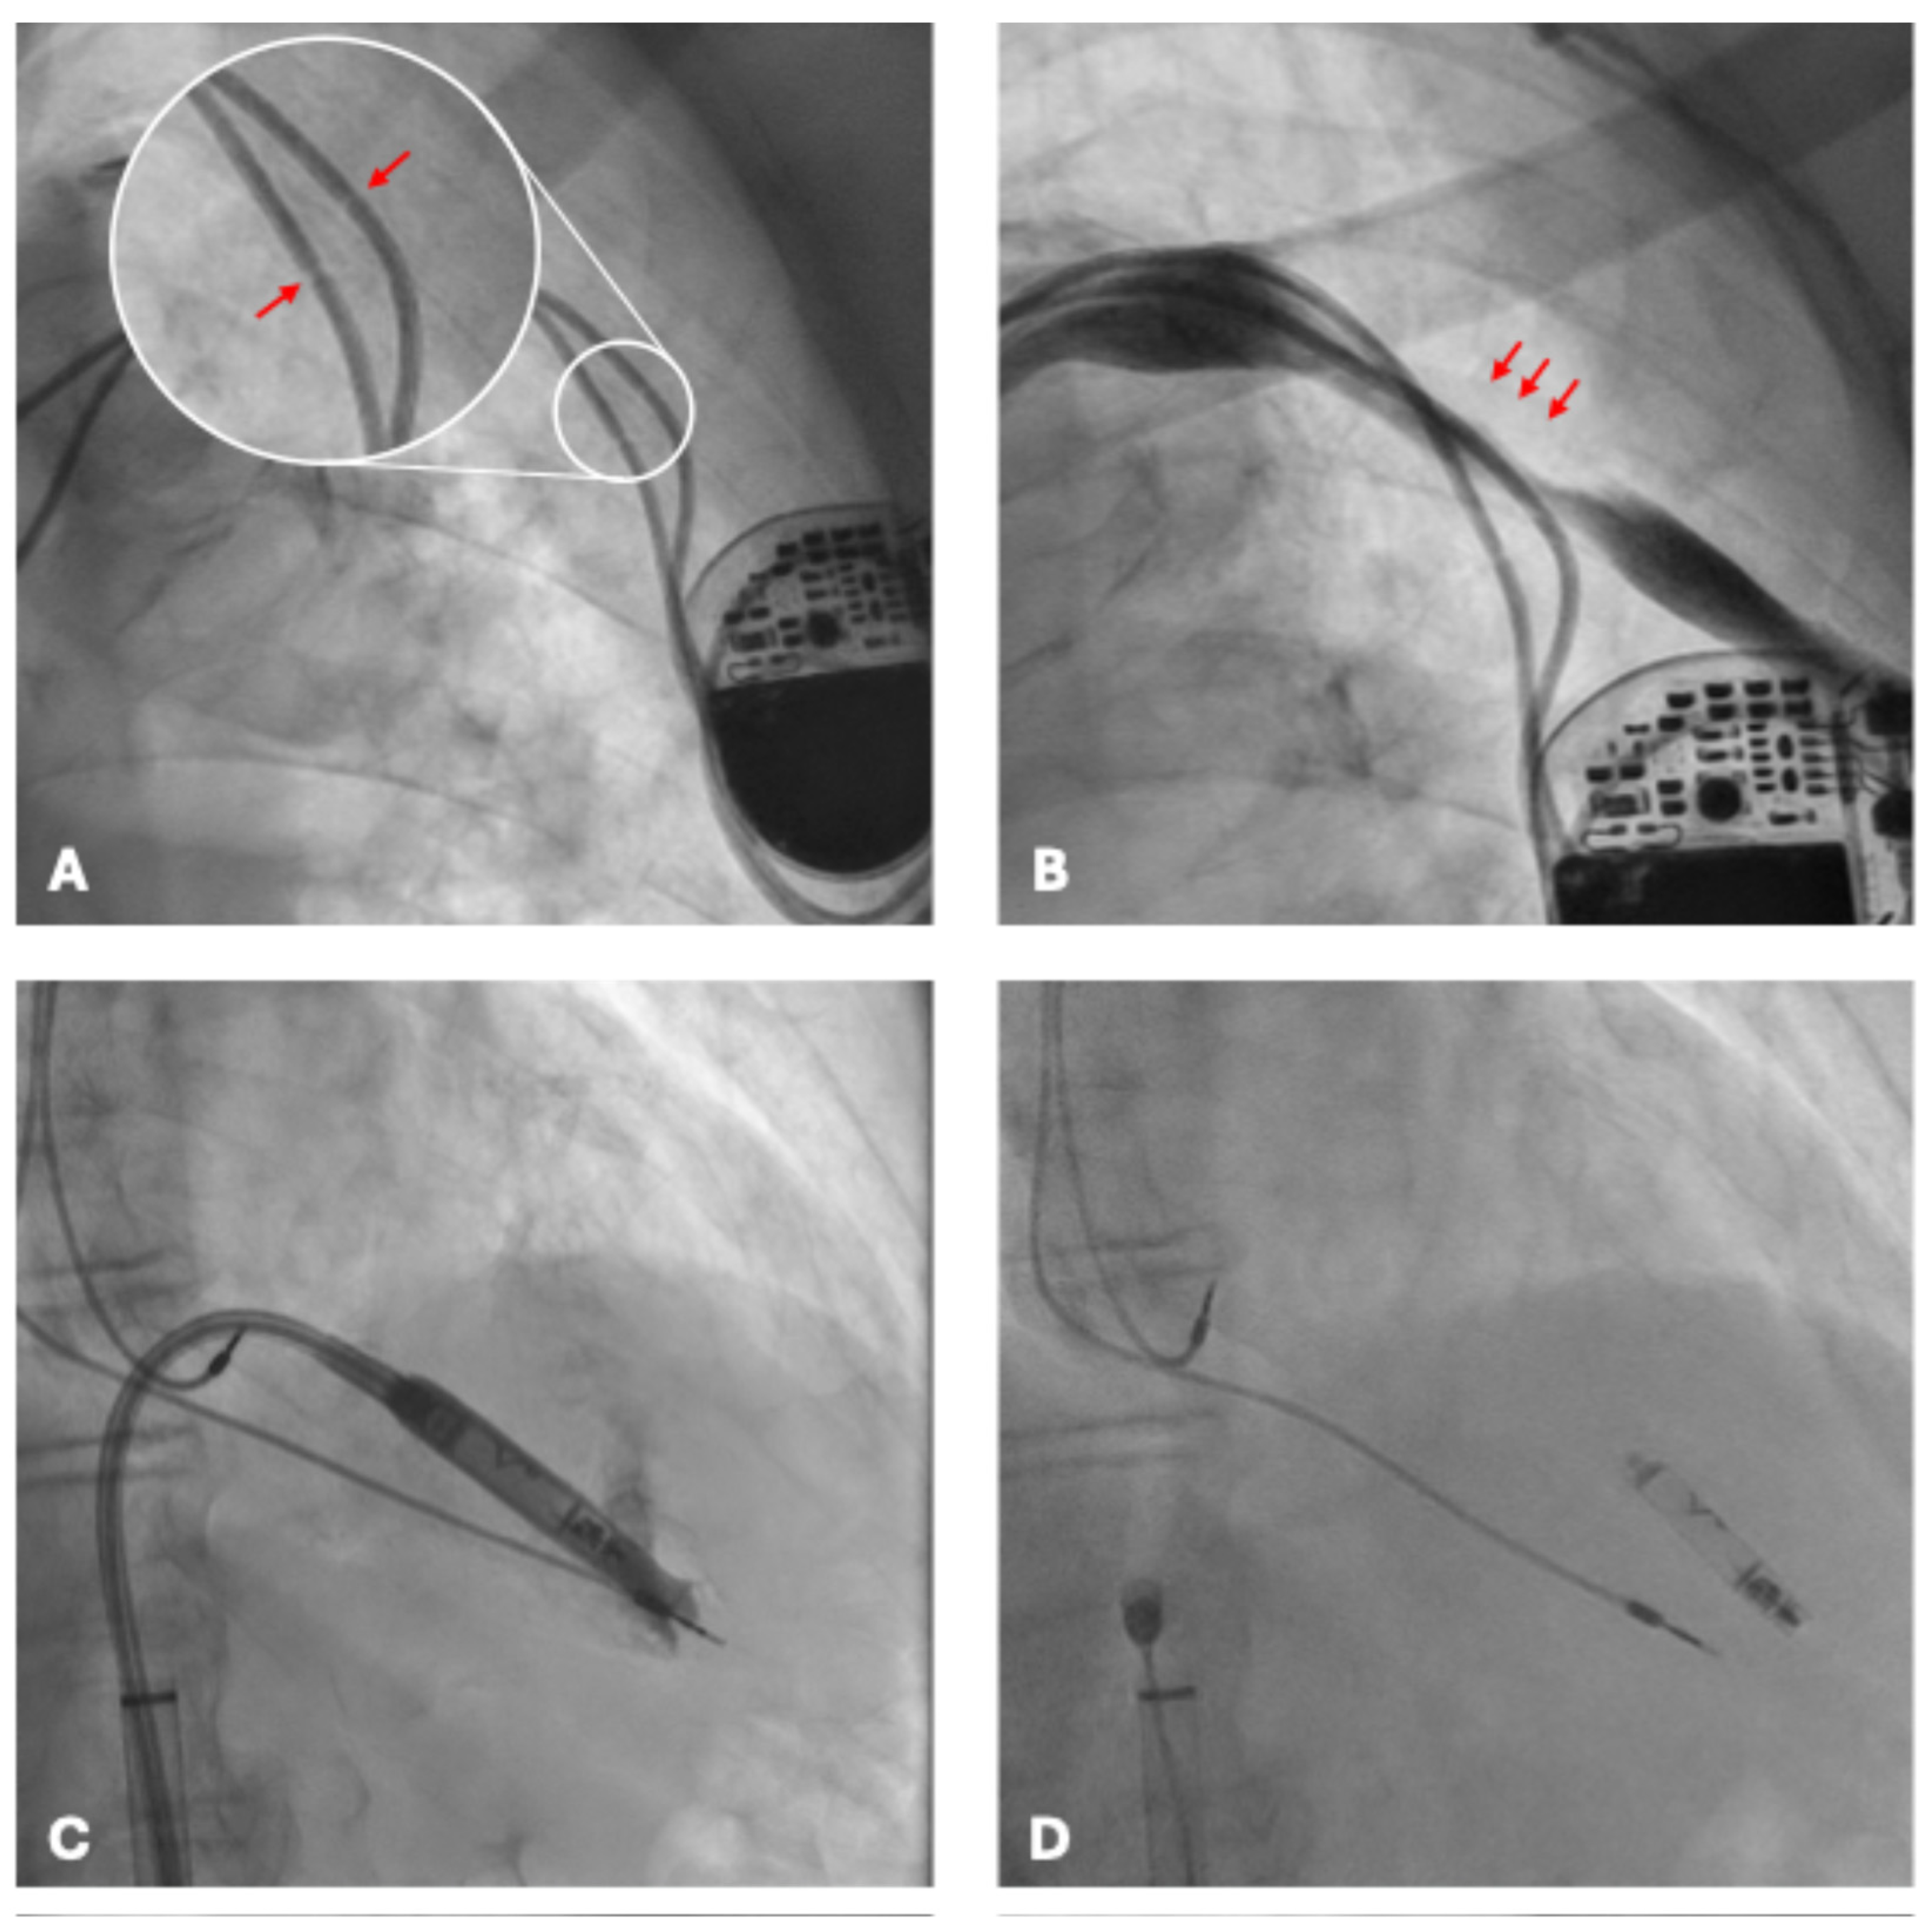

Fluoroscopic examination demonstrated the pacemaker generator in situ with both atrial and ventricular leads displaying focal narrowings in the infraclavicular region (Figure 2A). These findings were consistent with chronic mechanical damage, most likely related to suture fixation without protective sleeves at the time of implantation.

Conventional transvenous reimplantation was not feasible because of complete left subclavian vein occlusion (Figure 2B) and arterial overlap. Extraction of the damaged leads was deemed high risk. Leadless pacemaker implantation represented the only feasible and safe alternative, given the presence of complete venous occlusion, the high hemorrhagic risk of contralateral reimplantation, and the prohibitive risk of extraction. A leadless pacemaker (Aveir, Abbott) was therefore selected as the optimal solution.

The procedure was performed via ultrasound-guided right femoral venous access without interruption of anticoagulation therapy. The presence of pre-existing intracardiac leads posed technical challenges, obstructing advancement of the delivery system (Figure 2C) and requiring multiple repositioning attempts. After careful manipulation and sheath angulation adjustments, stable fixation of the leadless device was achieved on the apico-septal region of the right ventricle (Figure 2D).

Figure 2. Fluoroscopic images during evaluation and intervention. (A) Dual-chamber pacemaker with atrial and ventricular leads in situ; arrows indicate focal narrowing of the leads near the clavicular region, consistent with mechanical compression injury from suture fixation without protective sleeves. (B) Distortion of the venous course with focal narrowing (arrows) along the left subclavian vein, consistent with complete left subclavian vein occlusion, which precluded new transvenous access. (C) Advancement of the leadless pacemaker delivery sheath into the right ventricle, with interference from pre-existing intracardiac leads. (D) Final stable deployment of the Aveir leadless pacemaker on the apico-septal region of the right ventricle, with satisfactory positioning and electrical performance despite the presence of abandoned leads.